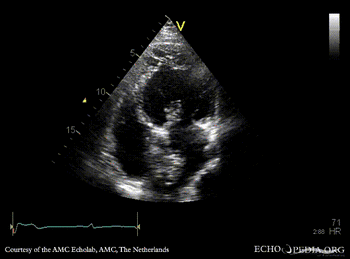

| A4CH | A2CH |